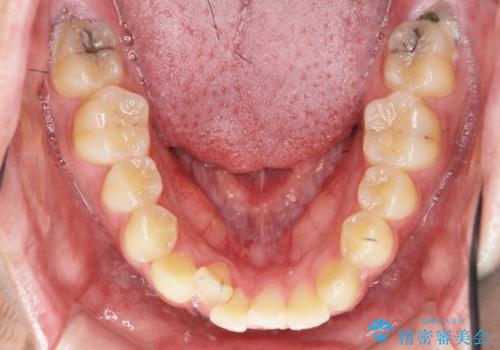

正中過剰埋伏歯で生じた前歯の審美障害 矯正治療での改善

- 前歯の見た目に悩まれて来院されました。

当初他院では、抜歯を行いセラミックブリッジを提案されていましたが、他の方法はないかと総合歯科治療を行う当院へと相談来院されました。

「時間がかかっても良いので、できれば歯を抜かずに矯正治療で治したい。」という強い希望があったので、矯正治療で歯並び・審美性の改善を計画します。